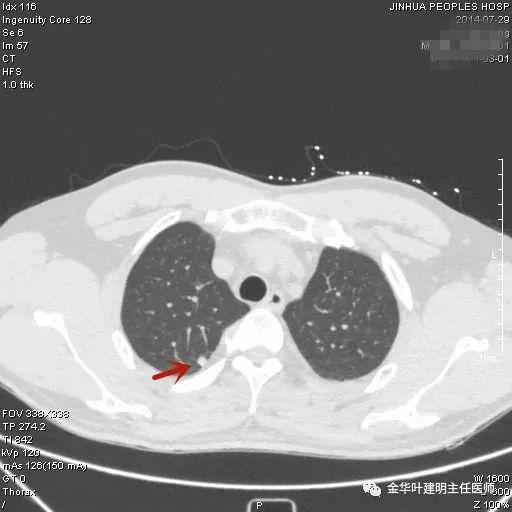

叶建明谈结节:检查发现肺实性结节怎么办?个人版实用指南

上图是肺内淋巴结。但我们看有明显血管进入病灶,胸膜似有牵拉,恶性的特征也不少。